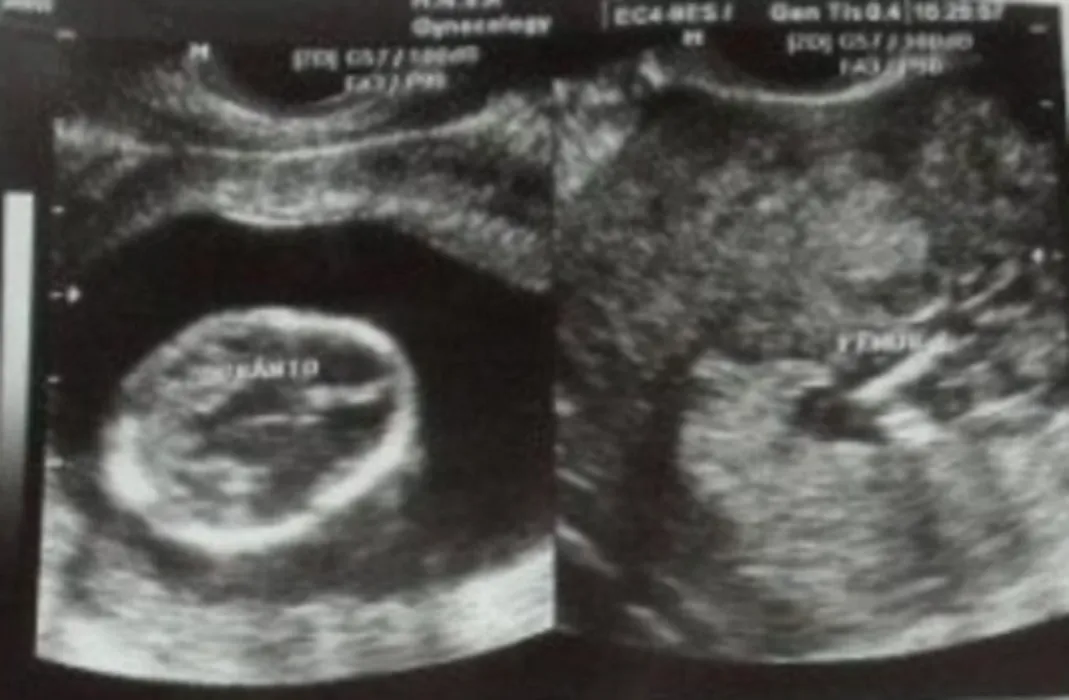

Ce surpriză a avut o gravidă când a făcut ecografie. „Semăna prea mult cu ea pentru a fi o coincidență”